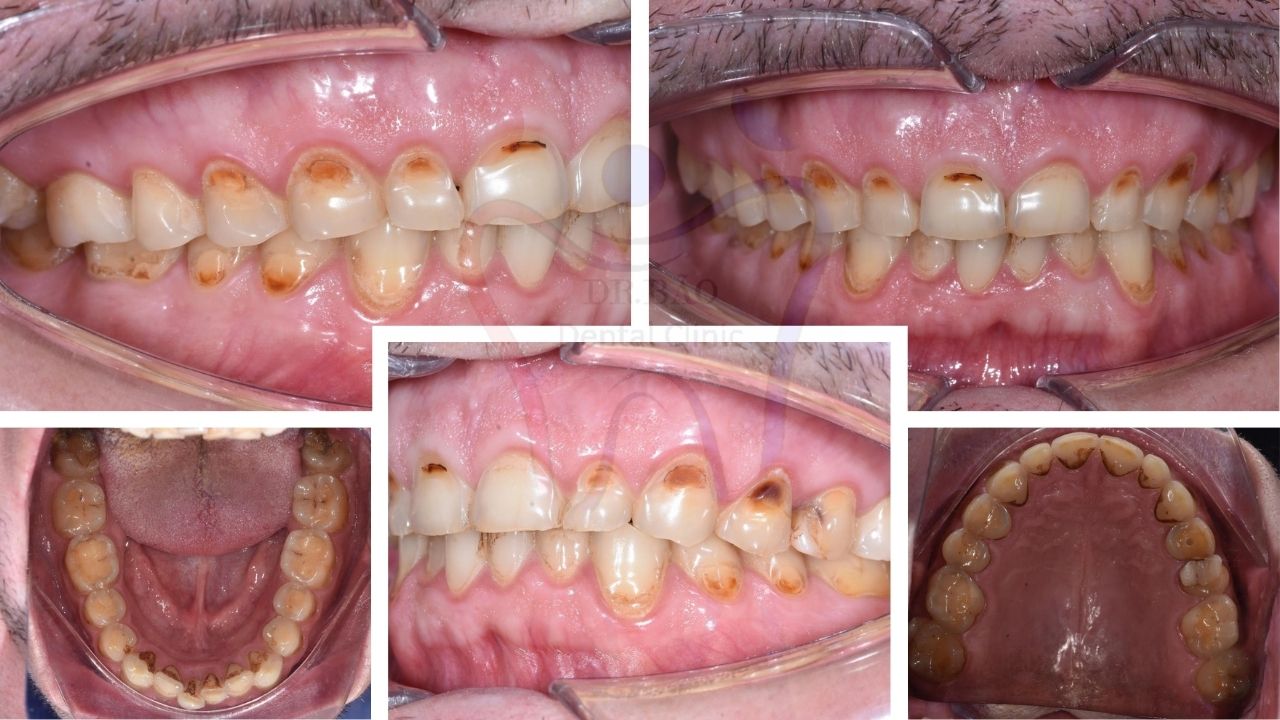

Our patient: Mr. Roman, 43 years old, from Russia.

After a clinical examination, we found that he was experiencing several issues:

Flattened & shortened teeth => Poor aesthetics.

Increased tooth sensitivity to hot, cold and sweet.

Visible dentin => yellowish layer is exposed => unaesthetic and sensitive teeth. We think he has the bruxism during the night.